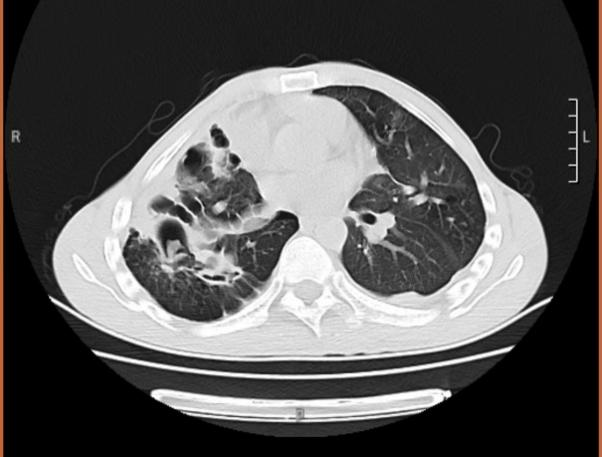

何飞仔细查阅了小王的肺部CT片,除了陈旧性肺结核病支气管扩张病灶外,部分囊状的支扩里面已有了典型的曲霉球病灶,进行多次痰真菌培养后,培养到了曲霉菌,并由此诊断其患上了“慢性肺曲霉病”。

何飞向小王解释,当时肺结核虽然治好了,但它的并发症却被忽视了。肺结核治愈后,因为长期的结核菌感染破坏,胸廓和气道结构会被不同程度破坏,若没有及时干预和长期管理,就容易出现像支气管扩张症、肺曲霉病等病症,医学界称之为结核后肺疾病(PTLD)。诊断明确后,何飞采用了中西医结合综合的治疗方案,一个月后复诊,小王的咯血基本停止了。